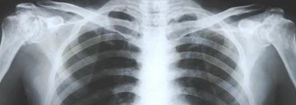

摘要:學好醫(yī)學基礎知識是學好醫(yī)學影像學的保證?,F(xiàn)代影像診斷是通過人體組織器官異常密度、回聲、頻譜及信號變化來反映病變存在的,這些不同的影像特征代表著疾病的病理演變過程。

學好醫(yī)學基礎知識是學好醫(yī)學影像學的保證。現(xiàn)代影像診斷是通過人體組織器官異常密度、回聲、頻譜及信號變化來反映病變存在的,這些不同的影像特征代表著疾病的病理演變過程。只有學好相關的基礎課程,才有可能學好醫(yī)學影像學。應學好化學、物理學、電子計算機等學科。有助于理解醫(yī)學影像設備的成像原理,正確使用各種檢查器械。應熟悉大體解剖和斷面解剖。有助于正確認識影像解剖鑒別正常、異常和變異,才能對病變部位準確的認識、定位和描述。應掌握病理解剖學和病理生理學。將病理基礎與醫(yī)學影像征象有機聯(lián)系將大大有助于對所見影像征象的理解與掌握,并對疾病做出正確診斷。

重視理論聯(lián)系實際是學好醫(yī)學影像學的關鍵。應重視實訓教學和實踐操作,在實踐中逐步培養(yǎng)自己分析、綜合解決問題的能力。應多看圖片、多看病例,設法搜集病例資源注意觀察閱讀正常影像表現(xiàn),培養(yǎng)對異常影像表現(xiàn)的辨別能力及描述能力,注重實習報告的書寫等基本功訓練,書寫報告時要求達到認識準確,語言精煉,并有分析鑒別,從而達到科學性、邏輯性、客觀性。